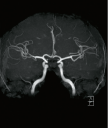

| 頭部MRI(磁気共鳴画像) | 頭頸部MRA(磁気共鳴血管画像) |

磁場の働きを利用して脳の血管を映し出す検査で、脳動脈瘤や太い血管の閉塞、狭窄などを見つけることができます。 |